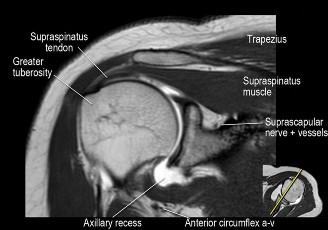

The correct answer is (B). An MRI showing a rotator cuff tear is considered diagnostic of a rotator cuff tear because of its high sensitivity, specificity, and accuracy. It has superb soft tissue imaging abilities (see Fig. 2–5). However, it should be noted that while MRI usually can differentiate between partial- and full-thickness rotator cuff tears, this varies with the power and accuracy of the MRI facility. This is also true with the ability of MRI to differentiate between partial-thickness rotator cuff tears and subacromial bursitis. An arthroscopy is needed for definitive differentiation of these pathologies.

Figure 2–5_Coronal oblique view MRI slice of a left shoulder. (Reproduced with permission from Smithius R and van de Woude HJ. Shoulder MR Anatomy: Normal Anatomy, Variants, and Checklist. _Radiology Assistant. April 2, 2012.)